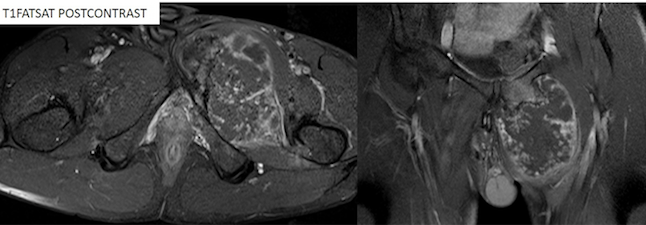

Figure 4. The lesion shows heterogeneous contrast enhancement.

The bulk of the tumor is noted to protrude into the medial aspect of the left upper thigh, elevating the gracilis and adductor muscle with altered signal intensity (hyperintense on T2WI, STIR) within it. On post-contrast study, the lesion shows heterogeneous enhancement.

Above findings of large cartilaginous matrix tumor with heterogeneous contrast enhancement, cortical expansion, and destruction suggests chondrosarcoma.